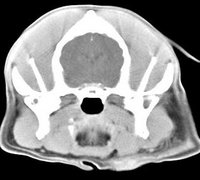

imágenes de TC en el perro | ||||||||||

ejemplo de imágenes de TC en el perro. Nótese la celulitis en la región parotídea izquierda | ||||||||||